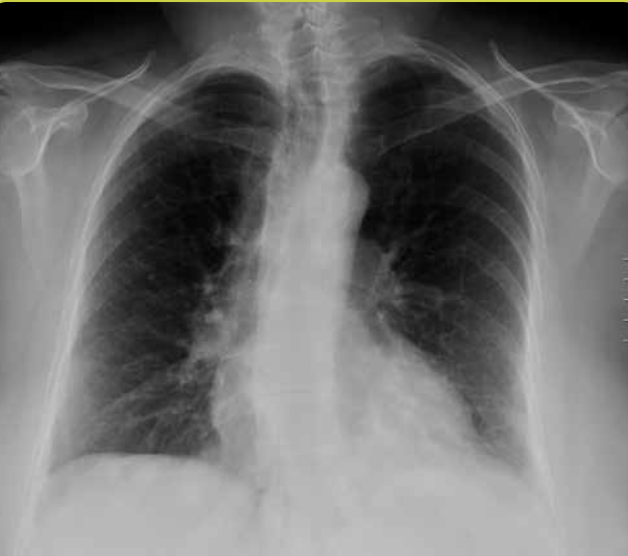

Rx normal.

Radiografía anteroposterior.

Hiperinsuflación. Patologías como el asma o el enfisema pueden cursar con un exceso de aire en los pulmones.

Sus hallazgos radiológicos son:

• Aplanamiento del hemidiafragma. Veremos el hemidiafragma derecho por debajo de la séptima costilla anterior.

• Horizontalización de costillas y aumento del espacio intercostal.

• Estrechamiento de la silueta cardiaca.

• Ensanchamiento del espacio aéreo retroesternal o retrocardiaco en proyección lateral.